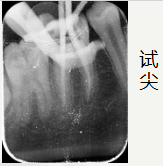

开髓后

依次使用

欧罗德卡 机用锉混号 的

开口锉15/08疏通锉15103过渡锉20/05成型锉25/06